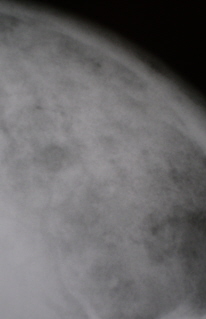

С целью выявления сонографических признаков, характерных для "миеломной почки", УЗИ почек проведено у 60 больных множественной миеломой, у 20 из которых заболевание диагностировано впервые. У 24 (40%) больных, главным образом миеломой Бенс-Джонса, обнаружено увеличение размеров почек. Толщина коркового слоя достигала 2-2,4 см. Выявлялась деформация (иногда раздвоение) чашечного комплекса и контура почек (рис. 9, 10). Расширялась чашечнолоханочная система. Лишь у 4 (7%) больных, страдающих множественной миеломой (у 3 больных миелома Бенс-Джонса и у 1 - G-миелома) в течение 5-7 лет, отмечено уменьшение размеров почек. Толщина их коркового слоя колебалась от 6 до 9 мм, наблюдалась деформация чашечного комплекса, расширение чашечек (>1,5 см) и лоханки (>4 см). При длительном течении болезни уплотнялся корковый слой из-за разрастания интерстициальной ткани (рис. 11). Оценивая результаты гематологического и урологического обследований, следует отметить, что у большинства больных множественной миеломой обнаруживалась гиперпротеинемия и протеинурия различной степени выраженности. По результатам пробы Реберга скорость клубочковой фильтрации (СКФ) у 15 (25%) больных была сниженной до 80-40 мл/мин (норма 80-120 мл/мин), а у 20% - 40-25 мл/мин, при этом минутный диурез составлял 0,5-1 мл/мин (норма 1-1,5 мл/мин). Креатининемия выявлена у 15% больных, а у 33% - установлено высокое содержание мочевины. Анализ реабсорбционной способности почек показал ее нарушение у 33% больных. У 40 (66,6%) пациентов (в пробе Зимницкого) заметно снижалась концентрационная функция почек.

УЗИ. Эхограмма почек больной, страдающей множественной миеломой 5 лет.

Рис. 11. Эхограмма почек больной, страдающей множественной миеломой 5 лет.

1 - почки левая и правая.